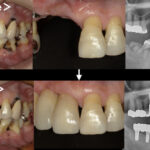

当院の精密根管治療 では、根管治療に精通した日本顕微鏡歯科学会認定医が十分な時間をかけて診療しております。また、様々な機器、薬剤を用いて、患者様の大切な歯をできる限り残すための環境を整えております。

マイクロスコープで視野を拡大することで、肉眼では見つけにくい病変を適切に処理し、治療箇所を長持ちさせるように心がけています。

当院では必要に応じて、保険診療であってもマイクロスコープを使って根管治療を行います。視野を拡大した細かい作業のため時間はかかりますが、再発を抑えて長期的にご自身の歯を使用できるような治療を心がけております。